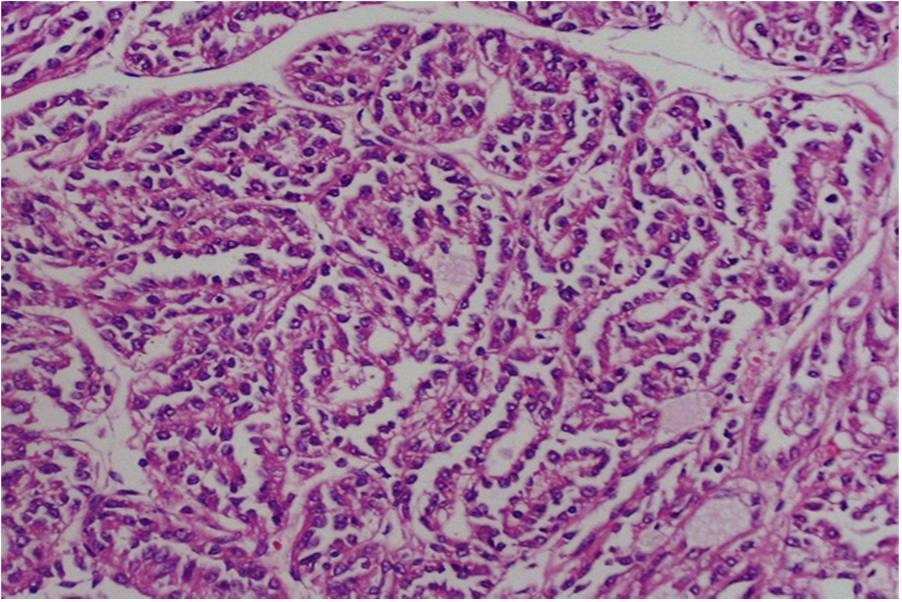

A rare renal neoplasm with dimorphic histology and mucinous stroma

Mucinous tubular and spindle cell carcinoma (MTSCC) is a rare and recently described histologic variant of renal cell carcinoma (RCC). Usually considered as a tumor of low malignant potential it is important to appreciate the characteristic histologic features to arrive at the correct diagnosis. We report a case of MTSCC in a female aged 54years who presented with a long standing vague loin pain. Diagnostic work-up showed a renal mass suggestive of RCC. With the preoperative diagnosis of RCC followed by nephrectomy showed a completely different histology of a rare tumour with tubules, spindle cells and mucinous stroma consistent with MTSCC, a low grade tumour with good prognosis.References